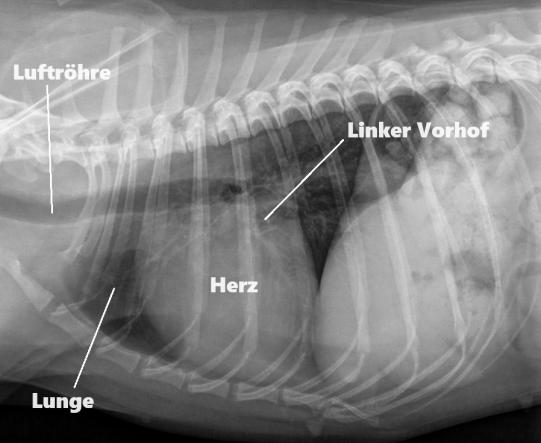

Im Röntgen ist ersichtlich, dass das Herz nur leicht vergrössert erscheint, die Lunge ist unauffällig.